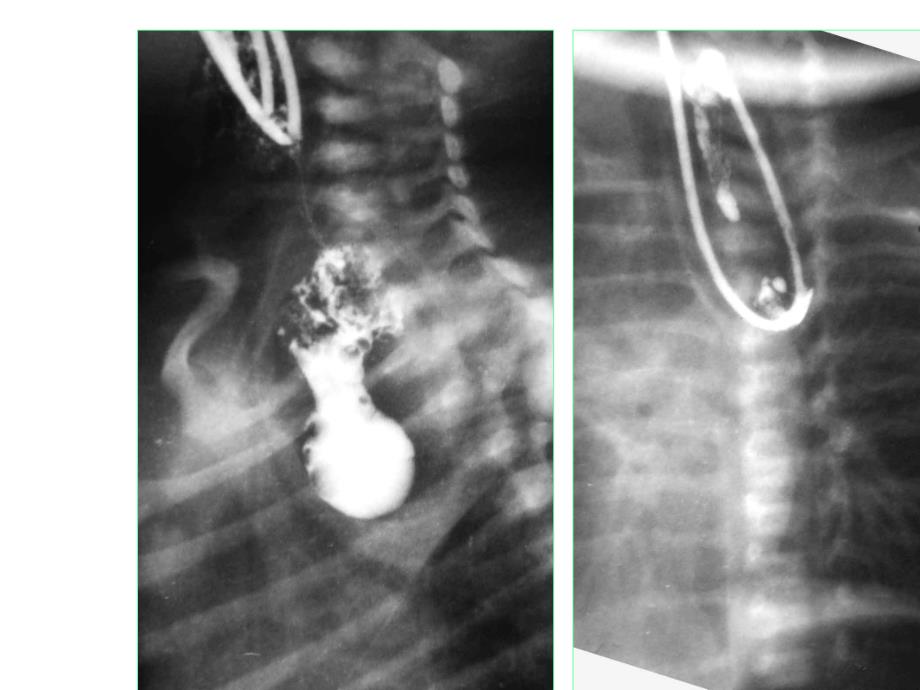

1、常见消化道畸形的影像诊断常见消化道畸形的影像诊断分五型分五型1.食管近远端均闭锁,无食管气管瘘。食管近远端均闭锁,无食管气管瘘。(6%)2.近端气管瘘,远端盲端。近端气管瘘,远端盲端。(少见)(少见)3.近端闭锁,远端气管瘘。近端闭锁,远端气管瘘。(85-93%)4.近远端均气管瘘。近远端均气管瘘。5.食管无闭锁,仅有食管气管瘘。食管无闭锁,仅有食管气管瘘。(2/4/5三型总计不超过三型总计不超过4%)尚有少见如:食管缺如、多处闭锁、近远端两尚有少见如:食管缺如、多处闭锁、近远端两瘘管、合并食管蹼等。瘘管、合并食管蹼等。食管闭锁后后术术术后12天,吻合口瘘。食管闭锁(术后)伴食管下段狭窄食管闭

2、锁(三型)伴十二指肠及肛门闭锁食管气管瘘 女,4月,T1水平。右为10岁复查片。食道裂孔疝食道裂孔疝 3月以内发病占60%,大于2岁仅占10%。主要症状为呕吐,半数带血丝。分四型1.滑疝2.短食管胸腔胃3.食管旁疝4.大型疝女,72岁,GI,食道裂孔疝概念胃扭转胃扭转 胃的部分或全部发生旋转导致胃的部分或全部发生旋转导致胃内梗阻胃内梗阻。胃扭转发病率男孩明显高于女孩,而且年龄越小发病率越高。呕吐是最主要的症状,可出现在任何年龄,约有一半患儿是在1岁之内出现,吐后仍有较强求食欲。胃扭转二、病因学分类1.原发性胃扭转:胃扭转是由于胃本身病变或韧带异常所致。胃本身病变包括:胃壁良、恶性肿瘤、胃过度胀